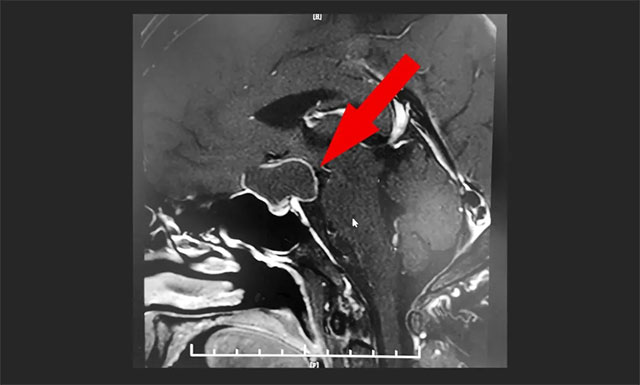

鞍區(qū)MRI平掃+增強顯示,鞍上區(qū)大囊樣占位,增強掃描薄壁強化,灶矢橫高徑約3*2*2cm;鞍上結(jié)構(gòu)(下丘腦、視交叉)均受壓,鞍隔下塌,鞍底腺垂體稍變扁,其左側(cè)份強化欠均勻。

潘仁龍主任、李士其教授、吳治群博士組成的專家組會診后考慮患者為顱咽管瘤復(fù)發(fā),腫瘤已明顯壓迫視交叉,出現(xiàn)視力模糊、視野缺損,手術(shù)指征明確。

▲ MR顯示鞍上區(qū)大囊樣占位